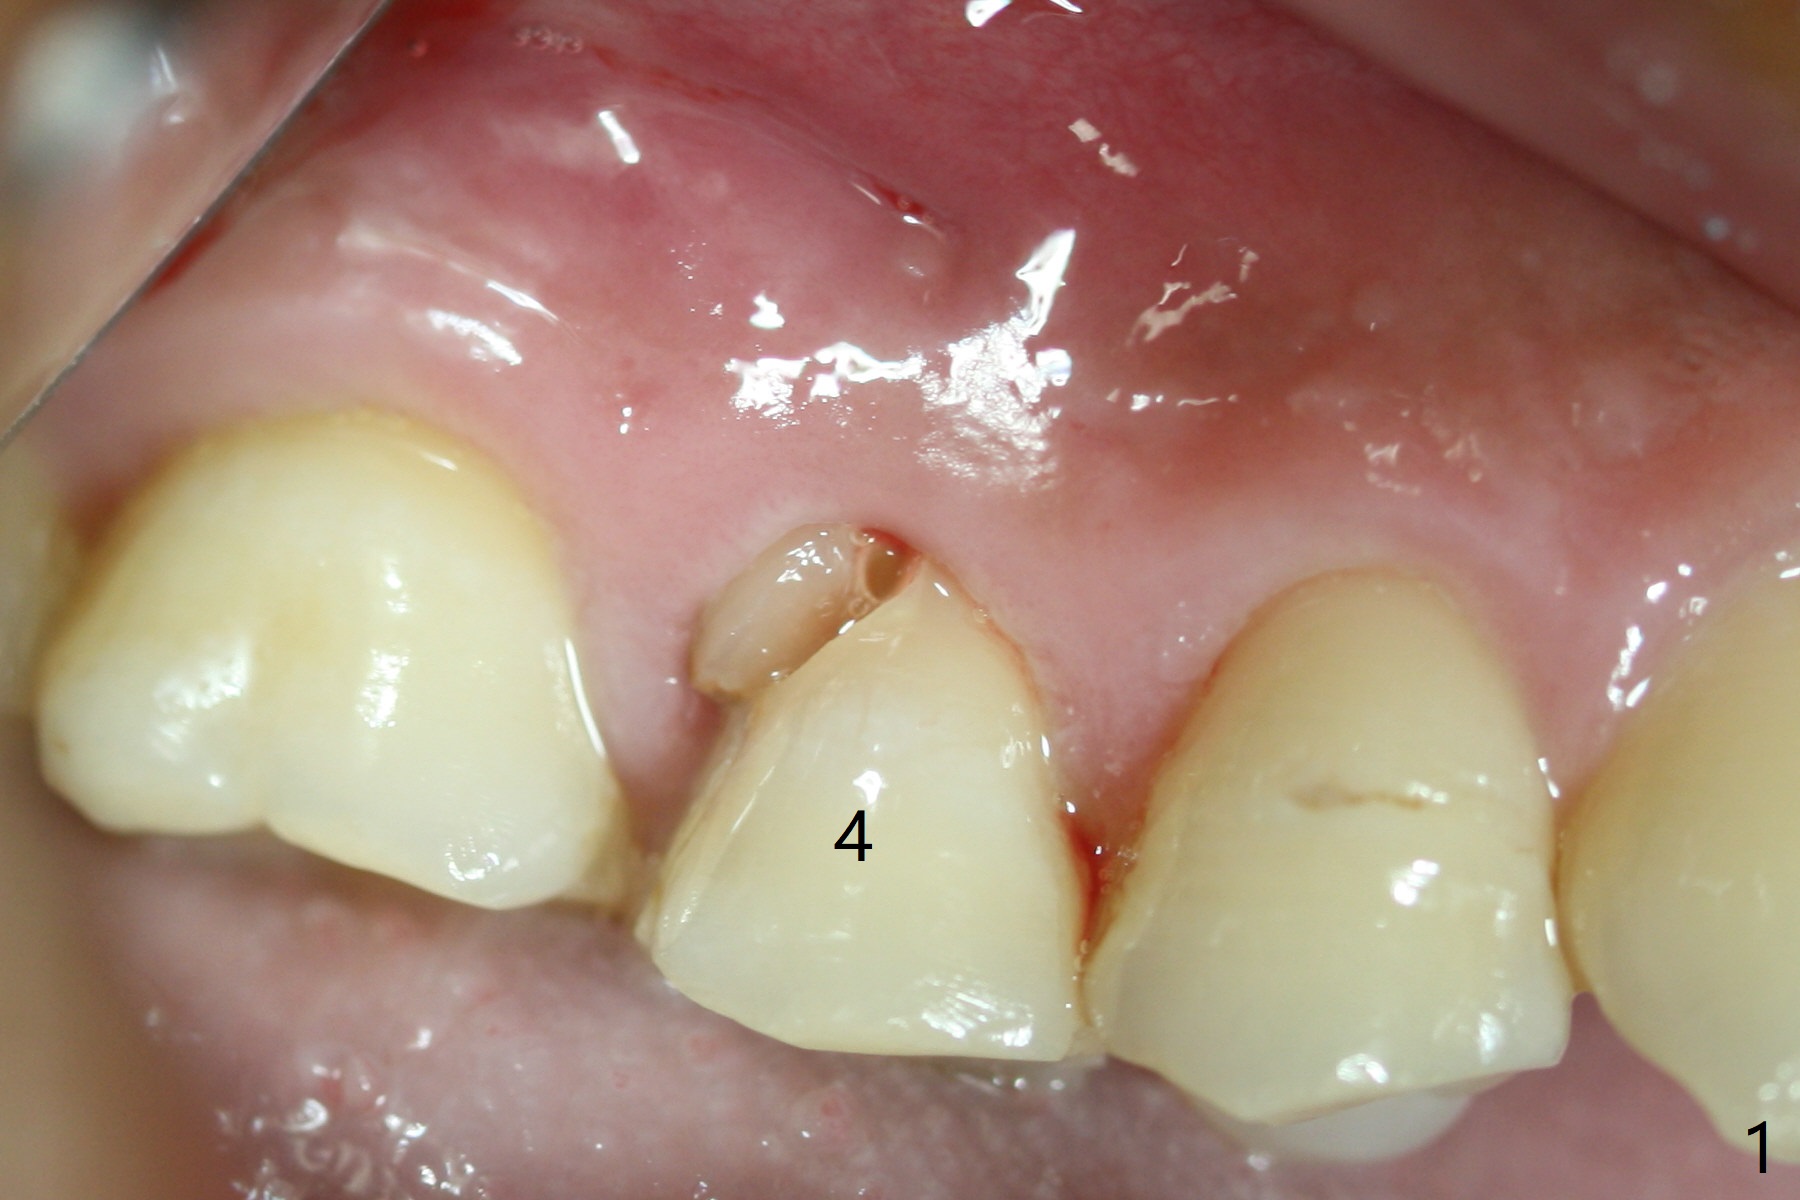

When the tooth #4 with vertical root fracture (Fig.1) is extracted, the buccal plate is found to be lost. The lowest point of the defect is shown as black dashed line in Fig.2 (yellow dashed line: sinus floor). After use of 2.5 mm reamer for 21 mm (buccal gingival level) and 3.0 mm reamer for ~17 mm, a 3.8x15 mm dummy implant is placed with 30 Ncm and 1.85 mm apical space (Fig.3 pink outline). A 3.8x18 mm (definitive) implant is placed with <40 Ncm with the implant plateau apical to the lingual crest (Fig.4,5). The buccal plate defect is repaired by Vanilla Graft (Fig.6 *) before and after insertion of a 4.5x4(3) mm abutment. The buccal plate defect seems to being repaired 4 months postop (Fig.7). Occlusal wear suggests bruxism, which is also associated with the root fracture. Night guard is recommended. The defect repair is close to completion 8 months post cementation (Fig.8). The crown/abutment is found to be loose 1 year 4 months post cementation and retightened without checking whether there is clinical 2nd DO caries of #3 (Fig.9, "sensitive to water pik"). A few days later, DO composite is being removed. It is difficult to determine whether the 2nd DO caries or gap has been removed with the neighboring crown in place. When the crown/abutment is removed and gingival retractions are inserted, there is no decay. The gap is removed. With Toflemire in place, the crown/abutment is reseated and hand tightened; after packable composite, the crown/abutment is removed, there is no more DO gap.